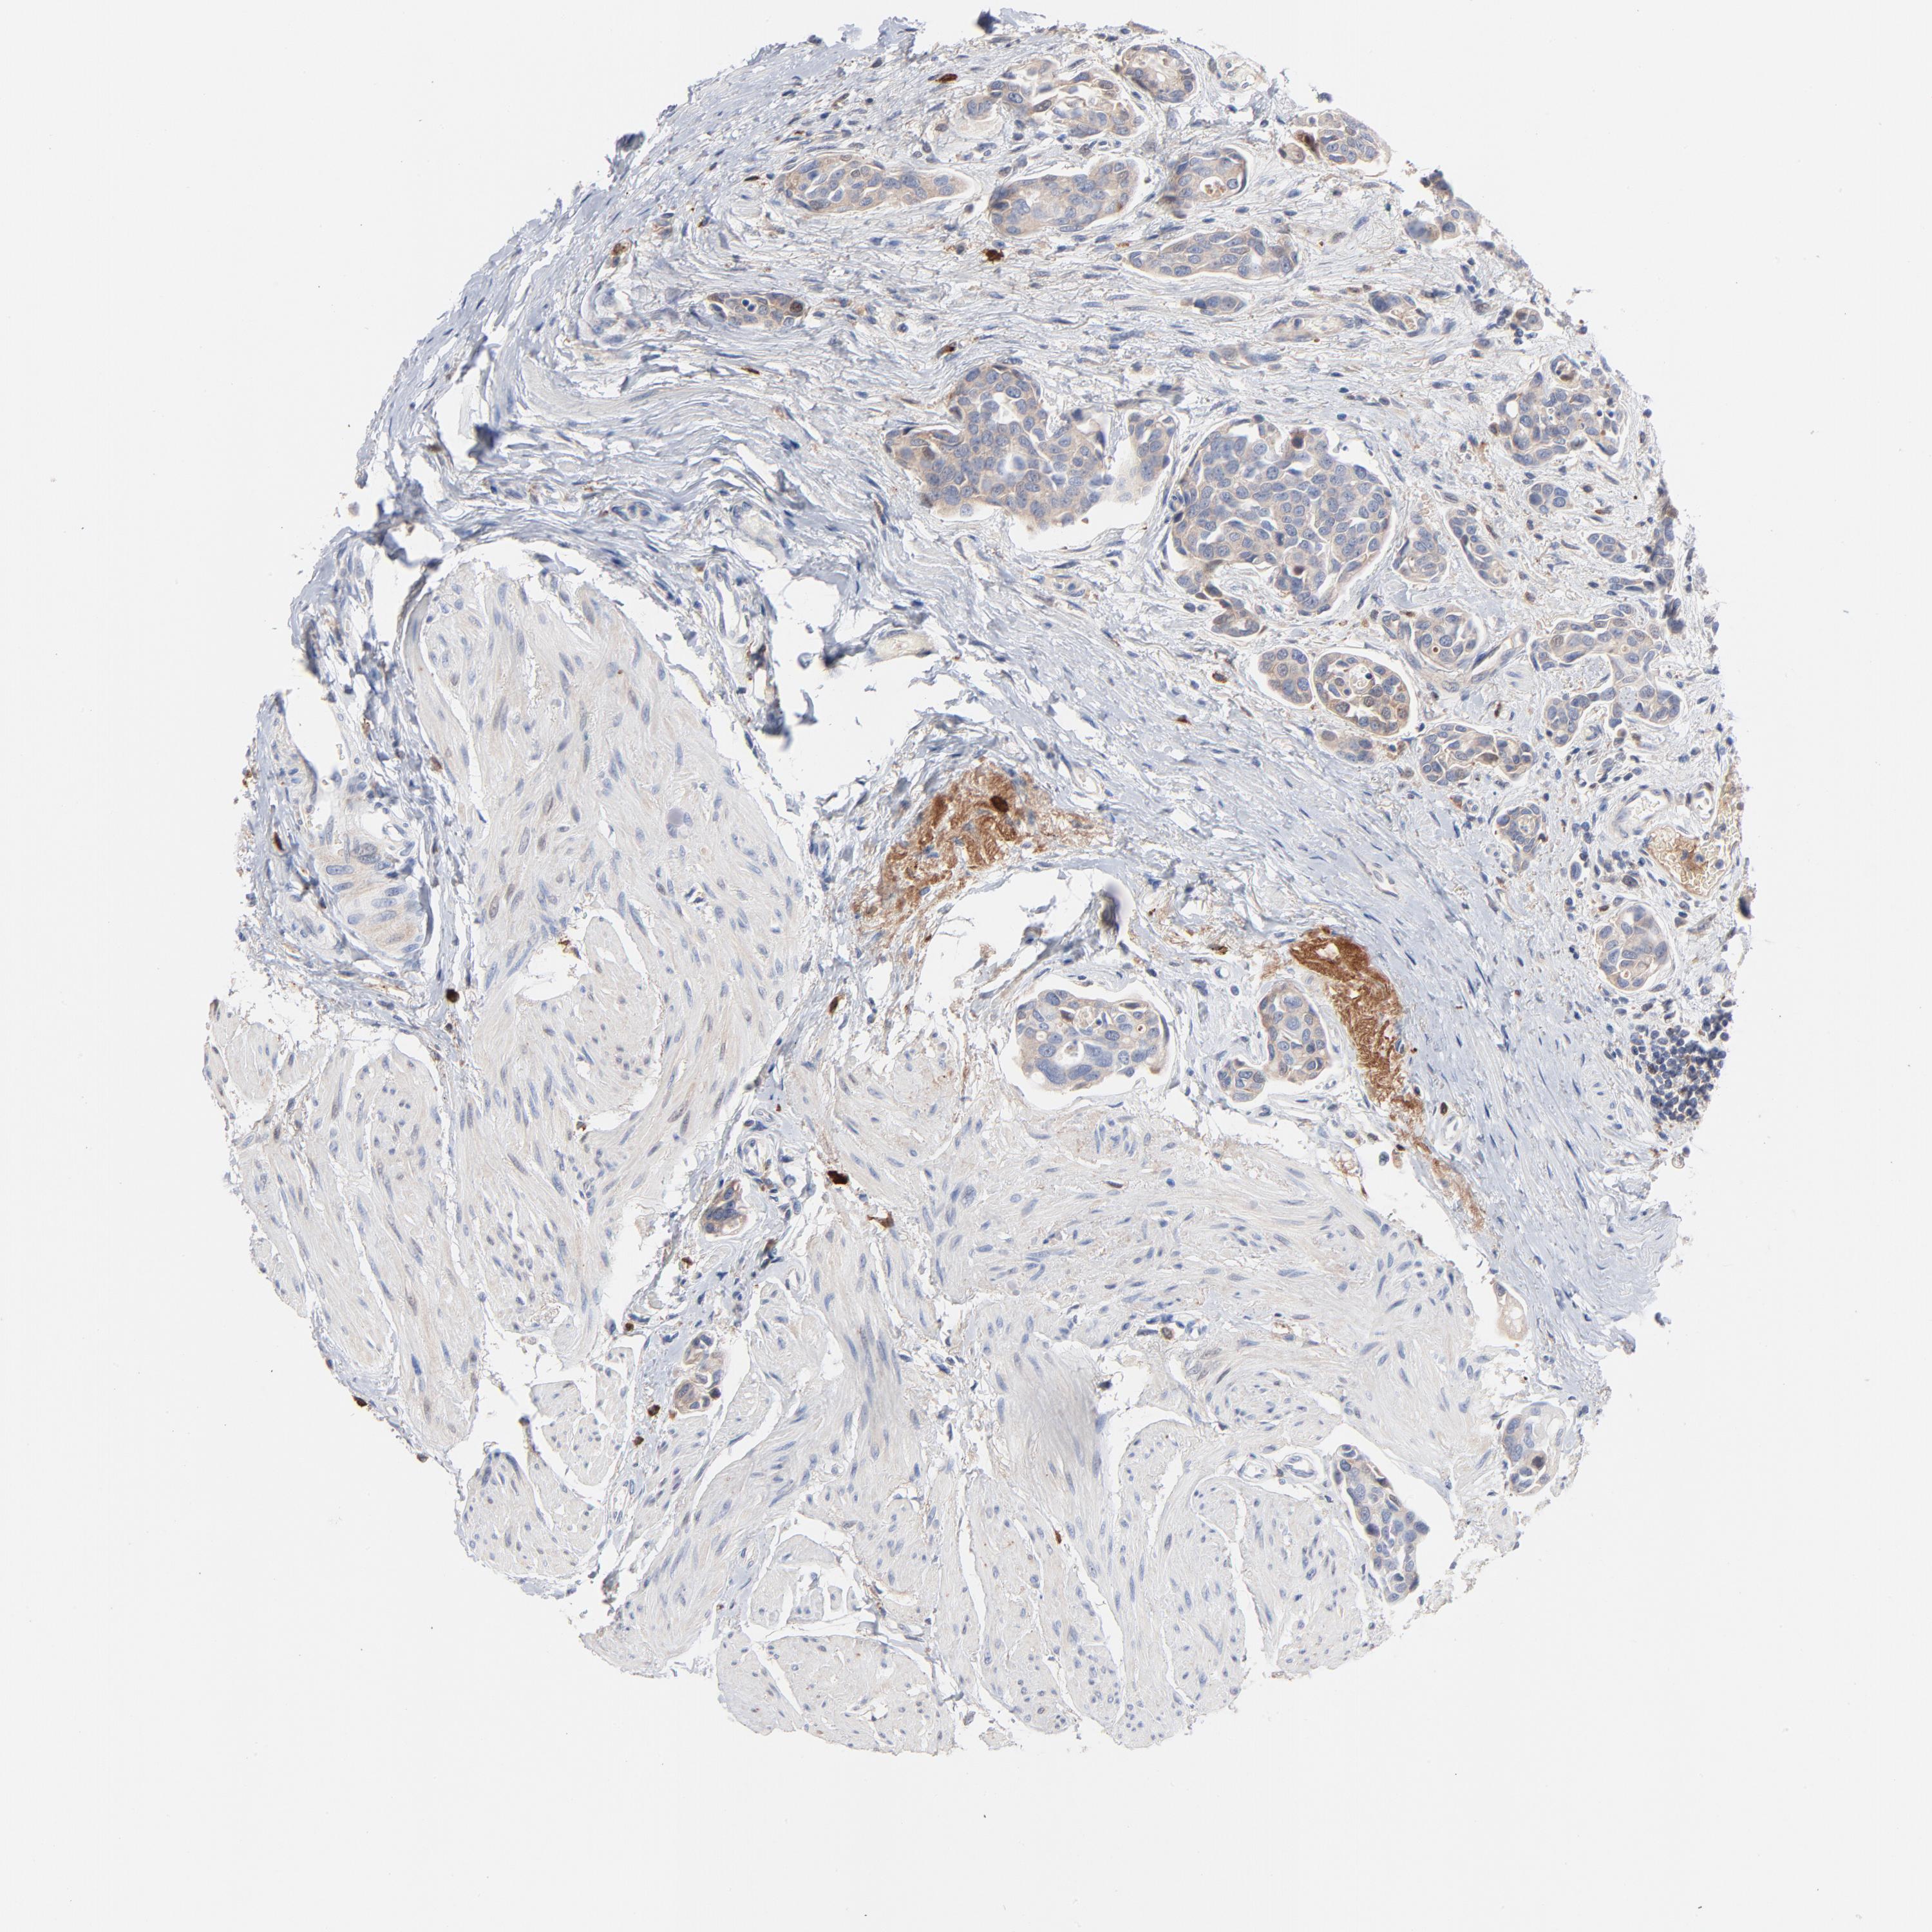

UROTHELIAL CANCER - Protein expressioni

A mouse-over function shows sample information and annotation data. Click on an image to view it in a full screen mode. Samples can be filtered based on level of antibody staining by selecting one or several of the following categories: high, medium, low and not detected. The assay and annotation is described here.

Note that samples used for immunohistochemistry by the Human Protein Atlas do not correspond to samples in the TCGA dataset.

Antibody stainingi

Antibody staining in the annotated cell types in the current human tissue is reported as not detected, low, medium, or high, based on conventional immunohistochemistry profiling in selected tissues. This score is based on the combination of the staining intensity and fraction of stained cells.

Each image is clickable and will lead to virtual microscopy that enables deeper exploration of all samples and also displays staining intensity scores, fraction scores and subcellular localization as well as patient and tissue information for each sample.

Antibody HPA003607

Staining

High

Medium

Low

Not detected

Intensity

Strong

Moderate

Weak

Negative

Quantity

>75%

75%-25%

<25%

None

Location

Nuclear

Cytoplasmic/membranous

Cytoplasmic/membranous,nuclear

Urothelial carcinoma, High grade